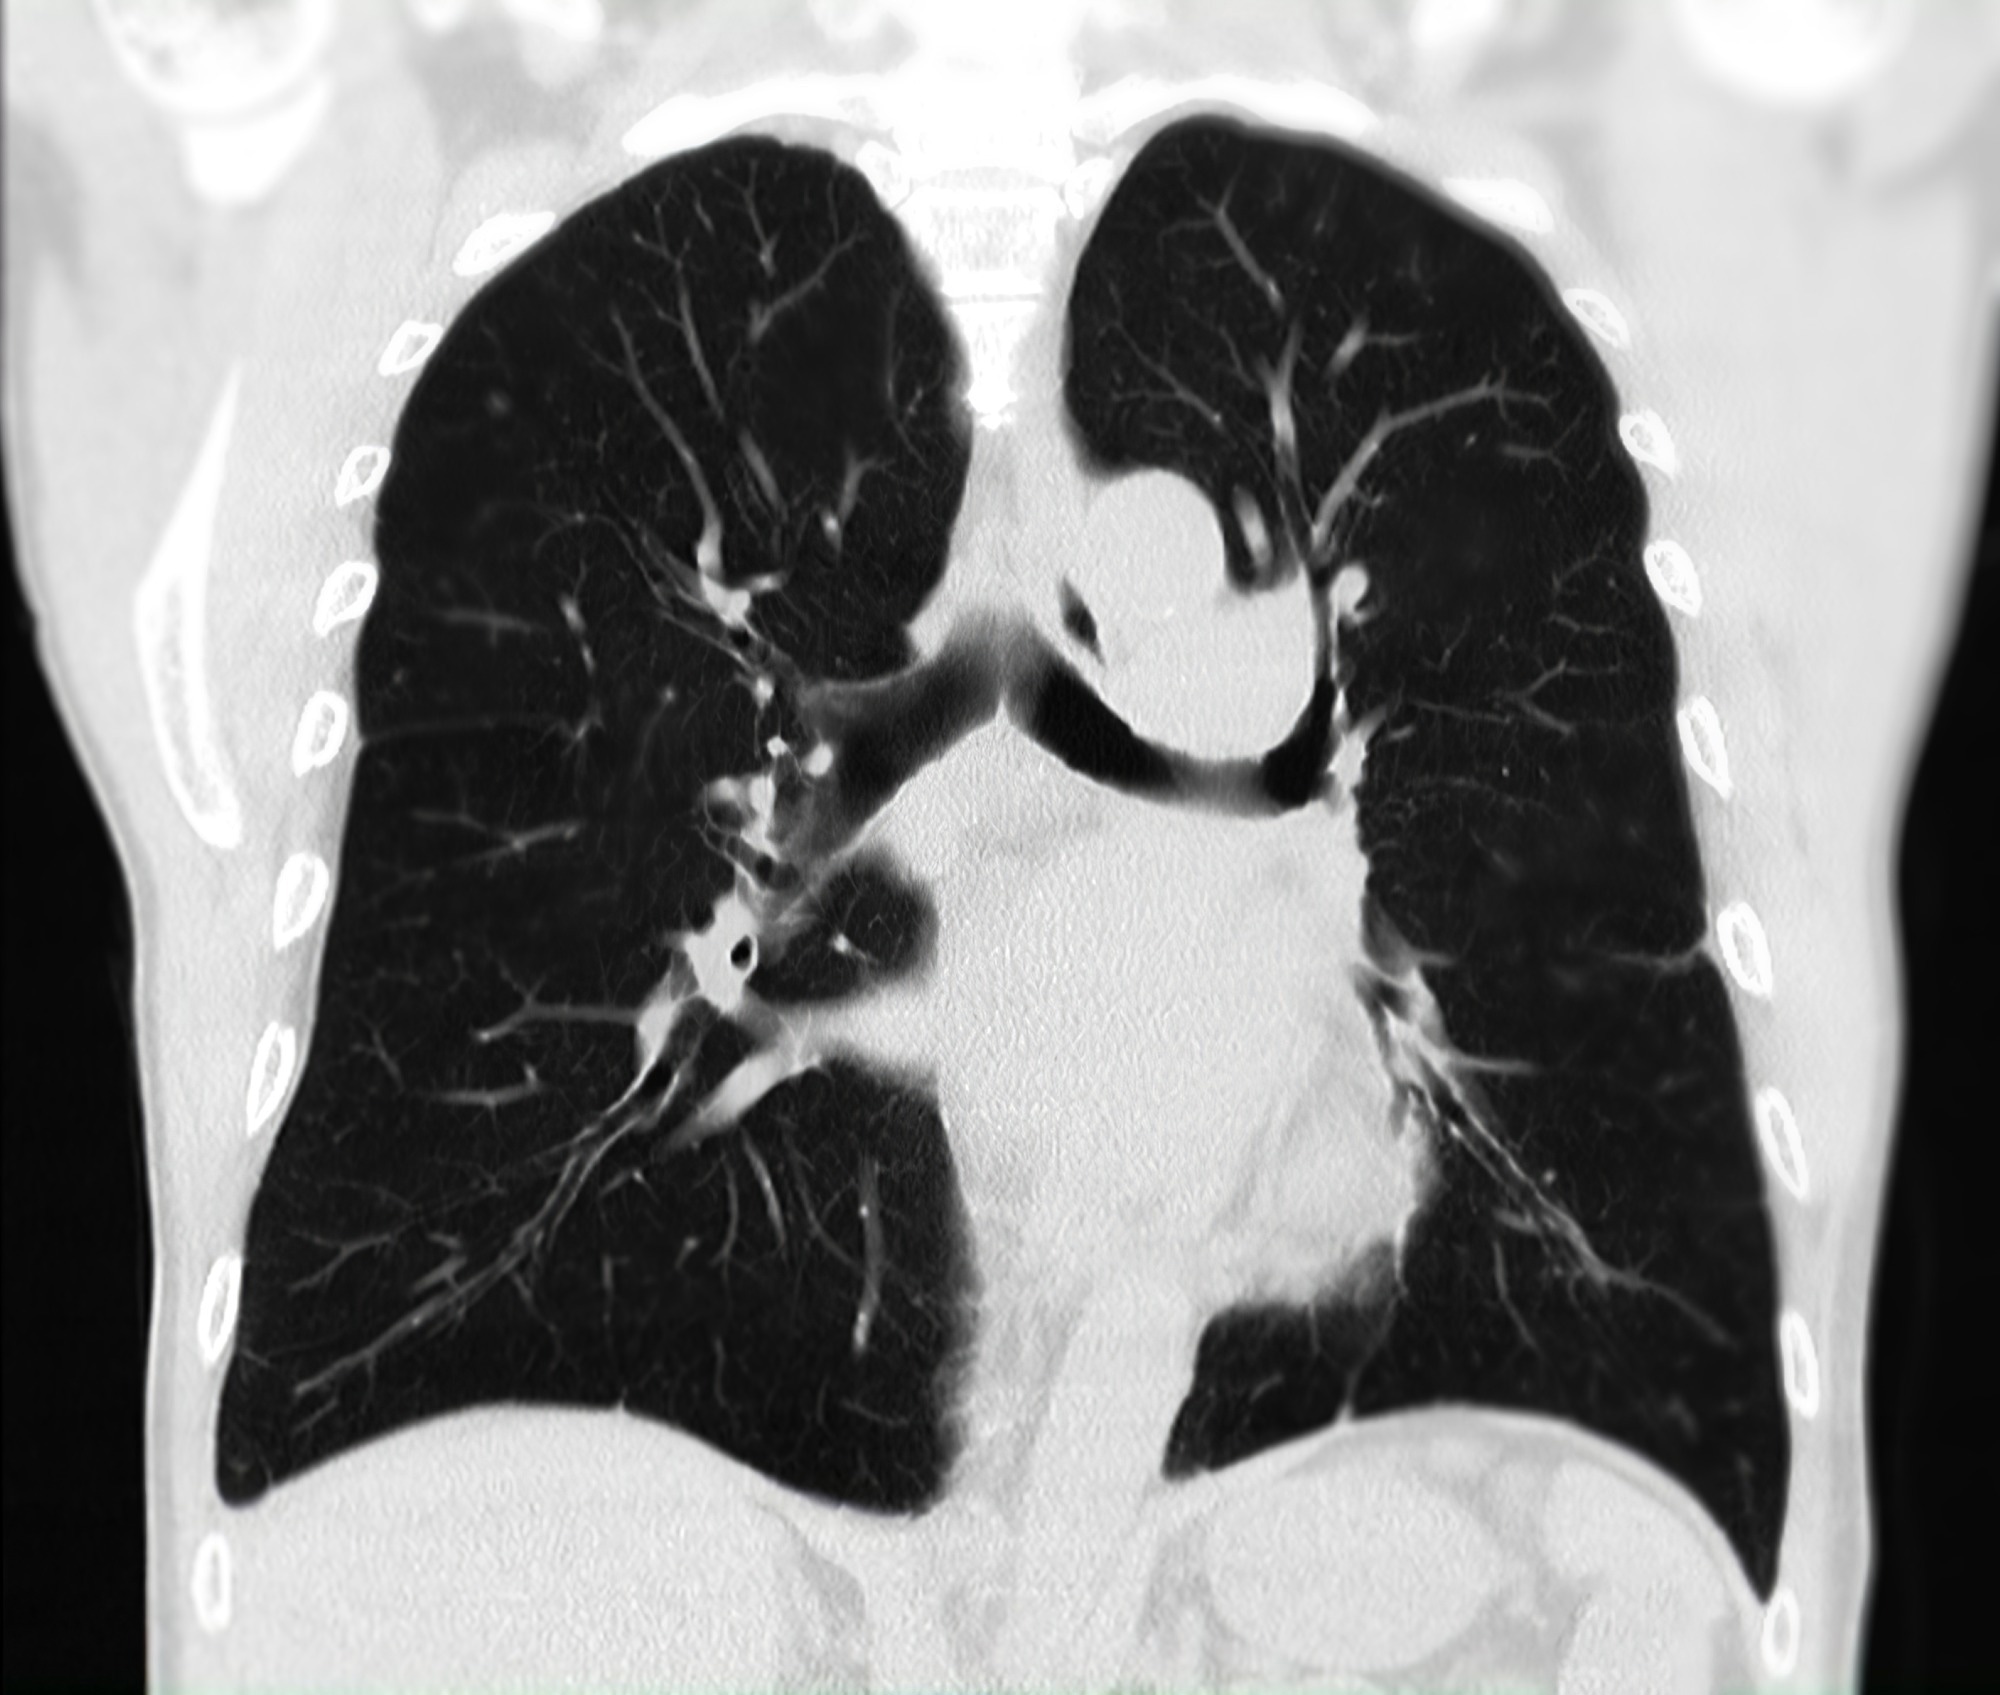

Avatar Medical turns routine DICOM data into clear, interactive 3D “avatars” that make anatomy instantly understandable, even when no radiology expertise is available, whether you’re a surgeon preparing a complex case or a patient trying to make sense of a diagnosis. Our work is about bridging the long-standing gap between what is shown in imaging and what is truly understood, and providing every clinician and patient with a shared, intuitive view of what’s happening inside the body.

Image credit: Avatar Medical